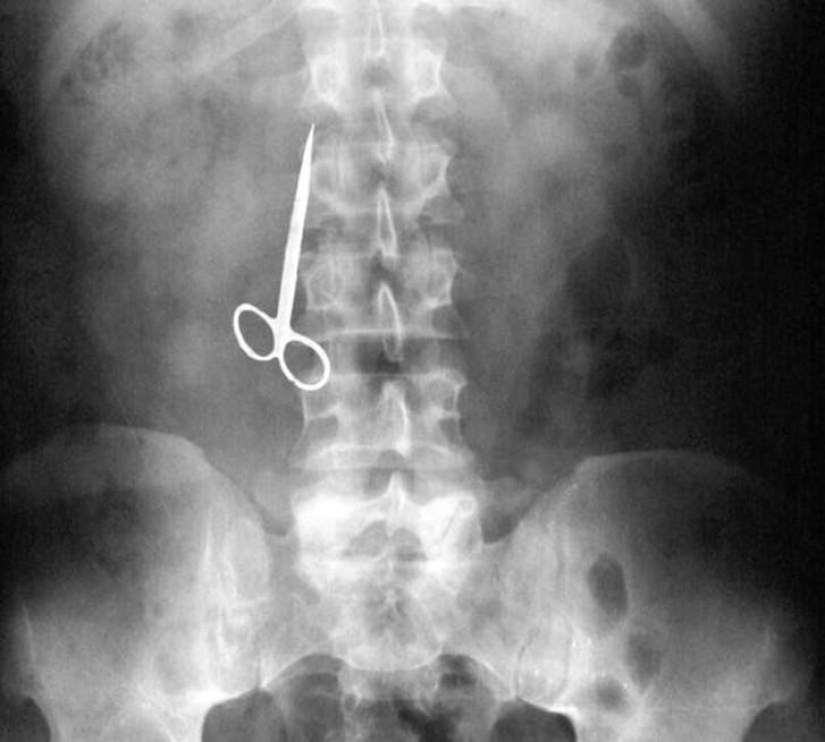

24. Scissors.